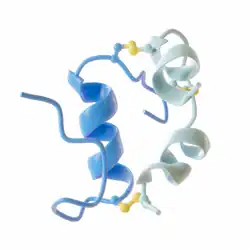

Insulin lispro, marketed under the brand name Humalog among others, is a modified form of medical insulin used to treat both type 1 and type 2 diabetes.[17] It is administered subcutaneously through injection or an insulin pump.[18][19] The effects typically begin within 30 minutes and last for about 5 hours.[17] Sometimes, a longer-acting insulin, such as insulin NPH, is also used.[20]

Common side effects include low blood sugar, while more serious side effects may include low blood potassium.[21] It is generally considered safe for use during pregnancy and breastfeeding.[22][23] It functions similarly to human insulin by increasing glucose uptake in tissues and reducing the amount of glucose produced by the liver in gluconeogenesis.[24]

Insulin lispro was first approved for use in the United States in 1996.[18][25][26] It is a synthetic analogue of human insulin, created by swapping two amino acids.[27] In 2022, it ranked as the 70th most commonly prescribed medication in the United States, with over 9 million prescriptions.[28][29] Insulin lispro is available under a generic label from Lilly.[30]